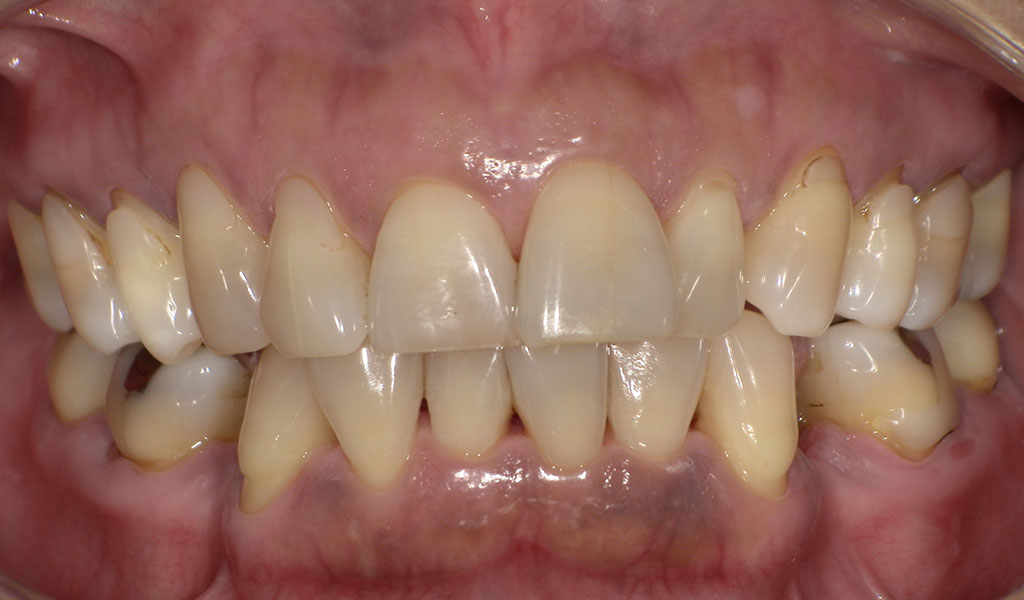

Before3

Before4